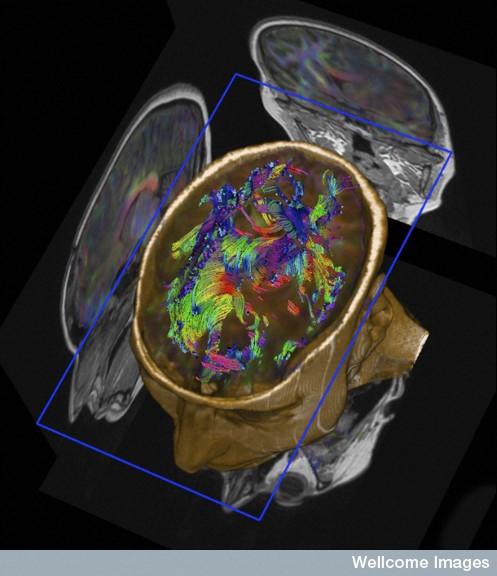

Johansen vil stikke hull på forestillingen om at naturvitenskapelige bildeteknologier er nøytrale og gir oss en umiddelbar tilgang til virkeligheten. Når vi for eksempel får se et bilde av den menneskelige hjernen der ulike farger viser ulik aktivitet i ulike deler av hjernen og bildeteksten lyder: «Slik ser menns og kvinners hjerner ut når de er stresset», er det langt ifra et nøytralt fotografi vi ser.

– Vår tiltro til vitenskapelige bilder og deres autoritet må sees i sammenheng med historiske oppfatninger om fotografiet som objektiv representasjon av virkeligheten, som sannhetsvitner om verden rundt oss. Disse forestillingene om fotografiet lever fortsatt videre i dag, og «smitter» over på måten vi forstår vitenskapelige bilder på. Samtidens vitenskapelige bilder er – i enda større grad enn andre bilder vi omgir oss med – brakt fram av en rekke ulike teknikker, som framhever, skjuler og avgrenser. Det brukes for eksempel fluoriserende markører som kan spores med lys, ulike former for mikroskopi som viser henholdsvis tverrsnitt og overflater av vevsprøver, samt omgjøring av todimensjonale bilder til tredimensjonale rekonstruksjoner. Det vi ser er en teknisk avansert og konstruert framstilling av virkeligheten, ikke en avduking av den, framholder Johansen.

Med sin bakgrunn fra kunst- og medieforskning er Johansen interessert i de vitenskapelige bildenes estetikk. Det er også vitenskapfolk selv. Mange av bildene hun tar for seg er hentet fra konkurransen Wellcome Image Awards.

– Her konkurrerer forskere og medisinske fotografer om hvem som har produsert, ikke bare om det mest vitenskaplige bildet, men også det mest slående bildet. Vakre farger, fine former og lekker komposisjon verdsettes, med den begrunnelse at dette er viktig i kommunikasjonen til offentligheten. Samtidig holder det ikke at bildet er fascinerende, det må også argumenteres for at det er nyttig, forteller Johansen. –Her spiller nok også bildets symbolverdi inn, slik som når et bilde av egg- og sædceller fra kunstig befruktning blir til et symbol på livets mysterium.